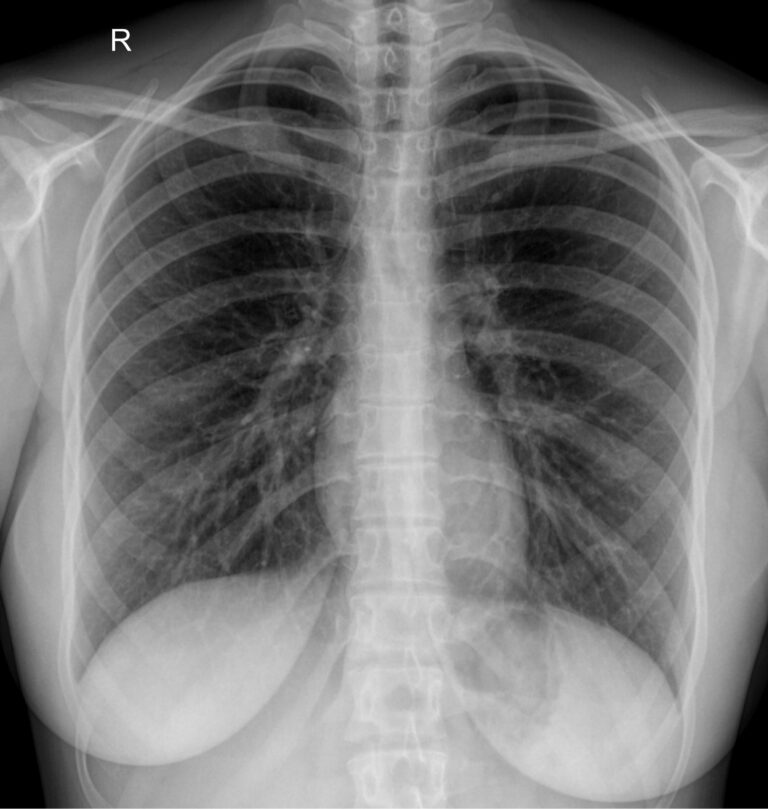

Снимок грудной клетки используют, чтобы получить изображение расположенных здесь органов: легких и дыхательных путей, контуров сердца с сосудами, а также позвоночника и костей. Обычно для диагноза достаточно одного снимка ― в прямой проекции, когда лучи идут сзади наперед. Иногда врач назначает снимок в боковой проекции, то есть слева или справа. Это необходимо, если требуется более точно определить сегмент поражения или достоверно исключить патологический процесс. Крайне редко требуются косые проекции, но они тоже бывают.

На рентгенограмме видны следующие образования, расположенные в грудной клетке:

• Мягкие ткани: грудные мышцы, кожные складки;

• Костный скелет: ребра, ключицы, грудина, нечетко ― позвонки, в пожилом возрасте ― хрящи;

• Легочные поля: определяются их прозрачность, симметричность, легочный рисунок;

• Корни легких: топография, форма, структура, ширина;

• Средостение: положение сердца и сосудов, формирующих его дуги;

• Купол диафрагмы: четкость, местонахождение;

• Синусы: свободные или заполненные.